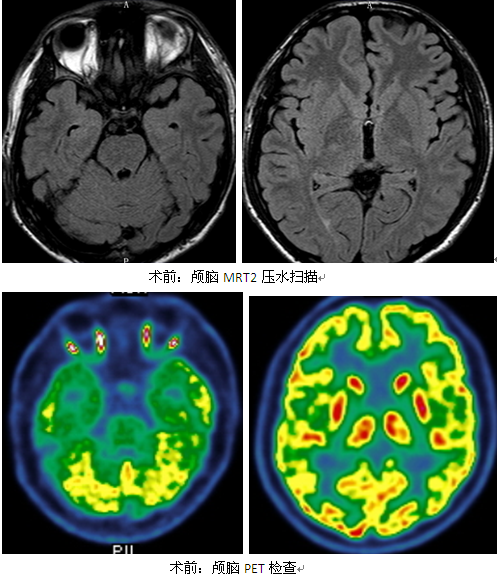

②1.5T颅脑MR 轴冠矢状位3mm T2压水薄扫磁共振,明确颅内结构情况:

右侧岛叶可疑信号增高;右侧颞极、右颞内侧结构可疑信号增高。

③颅脑PET:明确脑组织结构代谢,癫痫灶发作间歇期为低代谢。

右侧顶上小叶、缘上回低代谢;右外侧裂可疑低代谢。